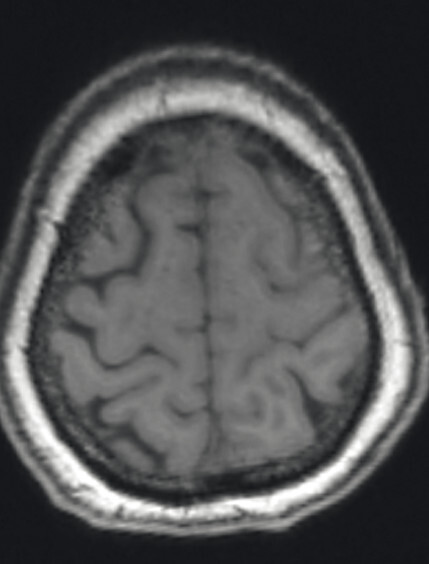

Abb. 69.11 Parkinson-Syndrome: Differenzialdiagnose kortikobasale Degeneration.

61-jähriger Mann mit rechtsbetonter Gliedmaßenapraxie, sodass Schreiben und Zeichnen nicht mehr möglich sind. MP-RAGE-Aufnahmen (a–c) zeigen eine deutliche Atrophie der linken Großhirnhemisphäre mit Ausziehung vor allem der Cella media des linken Seitenventrikels. Die voxel- und regionenbasierte morphometrische Analyse (d) bestätigt die Atrophie mit Betonung des Parietallappens. Die FDG-PET (e) zeigt einen Hypometabolismus der linken Hemisphäre mit Beteiligung von Thalamus und Basalganglien. Klinische Symptomatik und Bildgebung sind passend für eine kortikobasale Degeneration.

a Sagittale MP-RAGE-MRT-Sequenz.

b Axial reformatierte MP-RAGE-MRT-Sequenz.

c Koronar reformatierte MP-RAGE-MRT-Sequenz.

d Voxel- und regionenbasierte morphometrische Analyse.

e FDG-PET. (mit freundlicher Genehmigung von Prof. Dr. Dr. P.T. Meyer, Klinik für Nuklearmedizin Uniklinik Freiburg)